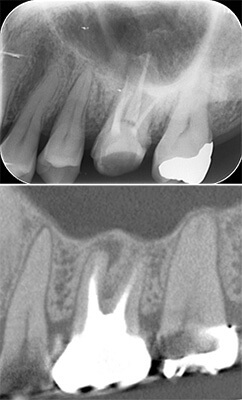

古い被せ物は色や形態が周りと合っておらず、また、被せ物の下には虫歯もありました。

期間はかかりましたが、患者様に非常に喜んで頂きよかったです。